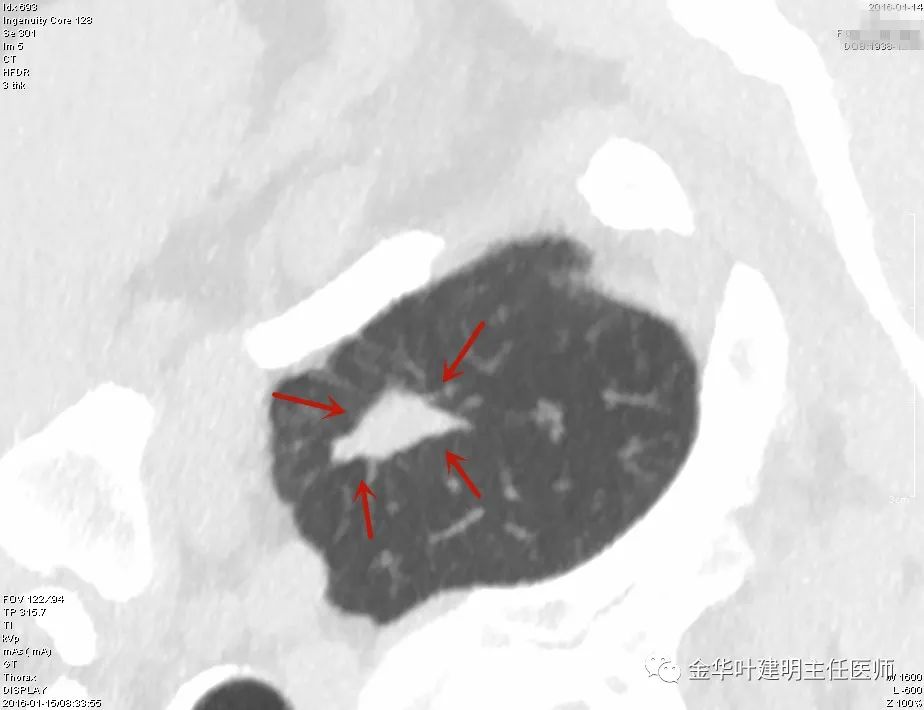

上图示鳞癌。病灶厚壁空洞,内壁凹凸不平,鳞癌可以乏收缩力,不一定有毛刺征或胸膜凹陷征。